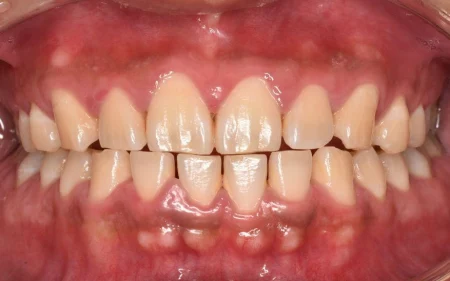

一般歯科 2023.0430代女性「歯のメインテナンスをしたい」目立つ着色を、専門的な歯のクリーニング「PMTC」とパウダーを用いた「エアフロー」できれいに落とし、本来の歯の色を取り戻した症例